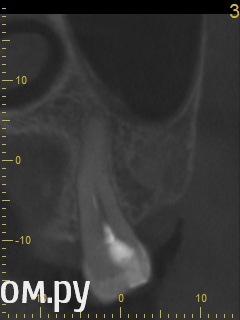

Анатолий М Опубликовано 21 апреля, 2014 Поделиться Опубликовано 21 апреля, 2014 Добрый день. Помогите пожалуйста.17 зуб (верхняя семерка с права). Пол года назад был депульпирован. Все это время присутствуют боли под этим зубом по симптомам очень похожие на кисту (распирание, боль ноющая не сильная, то появляется то сама собой изчезает. при перкуссии 17 зуб слегка болезненный). 2 месяца наза решили зуб перелечить. На ОПТГ ситуация до перелечивания. По снимку видно что первоначальное лечение было проведено плохо. Корни были плохо пройдены и плохо заполены цементом.Месяц хождения с гидроокисью кальция на воде никакого эфекта не дали. Врачи считают что под зубом есть киста. И предлагают удалить зуб. Так как перелечивание не помогло.Прилагаю снимок КЛКТ после лечения. Зуб все еще под временной пломбой. Из трех врачей лишь один разгледел на КЛКТ кисту под 17 зубом. Два других ни на КЛКТ ни на прицельных никакой кисты не видят. Направили к неврологу. Думают что киста если она и есть (в чем они не уверены) не дает имеющихся симптомов.Пожалуйста посмотрите на КЛКТ. Есть ли там киста или нет? И могут ли боли быть от нее?Заранее спасибо. Ссылка на комментарий

Анатолий М Опубликовано 21 апреля, 2014 Автор Поделиться Опубликовано 21 апреля, 2014 Снимок во время лечения делали? Коффердам и оптика использовались? На кт в тех срезах что Вы выложили кисты не вижу Снимки во время лечения делали три раза прицельные с иголками в каналах. Но они остались у врача. У меня их нет. Но она по ним кисты не видела. Коффердам использовали только при первом посещении когда вскрывали старую пломбу и прорабатывали каналы. При последующих посещениях при смене лекарст его не использовали так как кольцо на зубе плохо держалось и постоянно слетало. Плюс травмировало десну.Микроскоп использовали все три раза. По словам врача (врач высшей категории эндодонтист зав отделением):При вскрытии старой пломбы каналы практически не заполены цементирующим составом. Иструмент при вскрытии пломбы в каналы проваливался. Хотя стояла постоянна пломба. Из трех каналов лишь один был проработан до верхушки корня. Два других либо до половины либо на треть. Врачь полностью прошла все каналы и даже залезла за апекс. туда при первом пломбировании врач даже не пыталась лезть. При третьем посещении врач констатировала что каналы чистые. Никаких признаков инфекции нет. И белезненная перкуссия от чего то другого. Специально проводила ревизию каналов при втором и третьем посещении без анастезии что бы понять где болит. Но так и не поняла. Повела на консультацию к профессору в их стоматологи. Посмотрев контрольную КТ он сказал что там киста и надо удалять зуб! Похоже что мой врач с ним не очень согласна, хотя и спорить не стала поэтому отправила меня на консультацию к неврологу. Ниже срезы конрольного КТ после месяца лечения гидрооксидом кальция на воде. Срезы по дуге. Сделал как смог. Шаг срезов как я понимаю 1мм. Линия по перек дуги снимок номер 1 (см нумерацию в конце названия файла) Ссылка на комментарий

red_butler Опубликовано 21 апреля, 2014 Поделиться Опубликовано 21 апреля, 2014 Снимок во время лечения делали? Коффердам и оптика использовались? На кт в тех срезах что Вы выложили кисты не вижу Ссылка на комментарий

Гарриевич Опубликовано 21 апреля, 2014 Поделиться Опубликовано 21 апреля, 2014 Кисты по снимкам нет. Удалять зуб ,по снимкам, причин нет Ссылка на комментарий

DmitrySH Опубликовано 21 апреля, 2014 Поделиться Опубликовано 21 апреля, 2014 Аналогично, никаких признаков воспаления в костной ткани вокруг зуба не увидел. Ссылка на комментарий